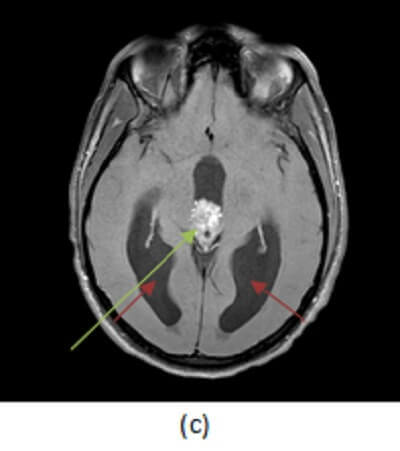

Figure 1: Pineal mass with heterogenous T1 (a, red arrow) and T2 (b, blue arrow) signal . The mass also heterogeneously enhances on post contrast T1 sequences (c, green arrow) and is associated with hydrocephalus (purple arrow).

Unlike pineal cell tumors, germinomas tend to “engulf” pineal calcifications, displacing them inwards. They are also typically associated with elevated serum markers. Germinoma’s account for about 60% of GCT’s, are associated with elevations in BHCG and occur disproportionately in young men. Situated in the midline around the third ventricle, they may involve sites other than the pineal gland, including the parasellar region and the basal ganglia. In fact, simultaneous pineal and suprasellar teratomas occur in 20% of cases. Germinomas have intense, uniform enhancement and may disseminate throughout the CSF. As a result, complete imaging of the brain and spine should be performed prior to treatment to evaluate the extent of disease. The presence of intra-tumoral cysts correlates with a worse prognosis. Treatment includes radiation and chemotherapy.

Masses in the pineal region can compress the third ventricle leading to hydrocephalus or compress the dorsal midbrain inferiorly resulting in paralysis of upward gaze and nystagmus from compression of the superior colliculus and oculomotor nucleus (Perinaud’s syndrome).